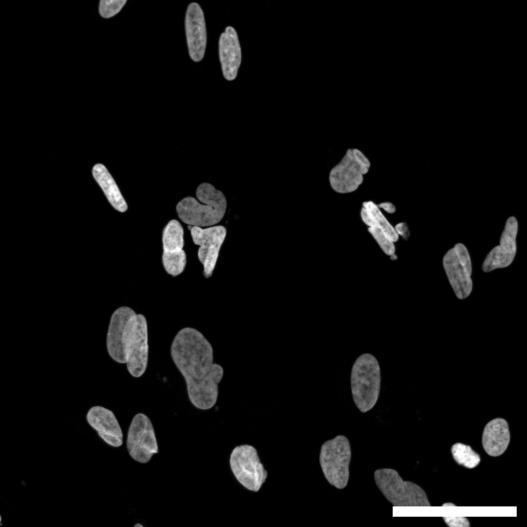

Fig 2 ACHP and Dexamethasone decrease TIC induced upregulation of GBP2 intensity and pro-inflammatory cytokines and growth factor release in hiPSC-derived astrocytes A) Representative images of hiPSC-derived astrocytes treated with Control or TIC and stained for the nucleus (DAPI, grey), Guanylate-binding protein 2 (GBP2, cyan or FIRE) and the astrocytic marker glial fibrillary acidic protein (GFAP, magenta) Z-stacks were acquired with a Zeiss LSM 880 confocal laser scanning microscope B) Quantification of the median GBP2 intensities in control and TIC stimulated cells Confocal images were acquired with an Opera Phenix High Content Screening System (PerkinElmer) and image analysis was done using Harmony 5 2 software Data presented as mean ± SEM for n = 3 biological replicates P-values generated by a two-way ANOVA with Dunnett post-test for multiple comparisons to Control+TIC P ≤ 0 05 (*), P ≤ 0 01 (**), P ≤ 0 001 (***), P ≤ 0 0001 (****) C) Representative confocal laser scanning microscope image of hiPSC-derived astrocytes indicate a change in morphology for GFAP (cyan) under TIC conditions D) Quantification of CXCL10, IL-6, YKL-40, CCL2, CCL5, GM-CSF and VCAM-1 secretion performed on astrocyte conditioned media using LUMINEX or ELISA N=3 P-values were generated by a One-way ANOVA with Dunnett post-test for multiple comparisons to Control+TIC Exception: P-value for YKL-40 (Control vs Control+TIC ) was calculated by unpaired t-test (mean±SEM) Abbreviation: Dexamethasone (Dex) E) Use of the NFkB reporter in astrocyte reactivity model Images were acquired and analysed using and Incucyte SX3 N=1; P-values were calculated by unpaired t-test (mean±SEM)